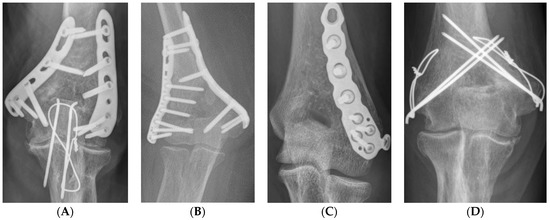

All surgeries were performed in the supine position under general anesthesia using a tourniquet. Each approach was performed using standard methods [14,15,16,17]. In the posterior approach, the ulnar nerve was first identified and protected. In cases of severe intra-articular fracture fragmentation, olecranon chevron osteotomy is performed. Subsequently, depending on the surgeon’s preference, either orthogonal, parallel, or single 3.5 LCP distal humerus plate (DuPey Synthes, West Chester, PA, USA) fixation or TBW fixation was performed (Figure 1A–D). Anatomical reduction was implemented as much as possible to achieve absolute stability, and at least three cortical or locking screws were inserted proximally and distally.

Figure 1.

Fixation method (A) orthogonal plate, (B) parallel plate, (C) single plate, (D) tension band wiring.